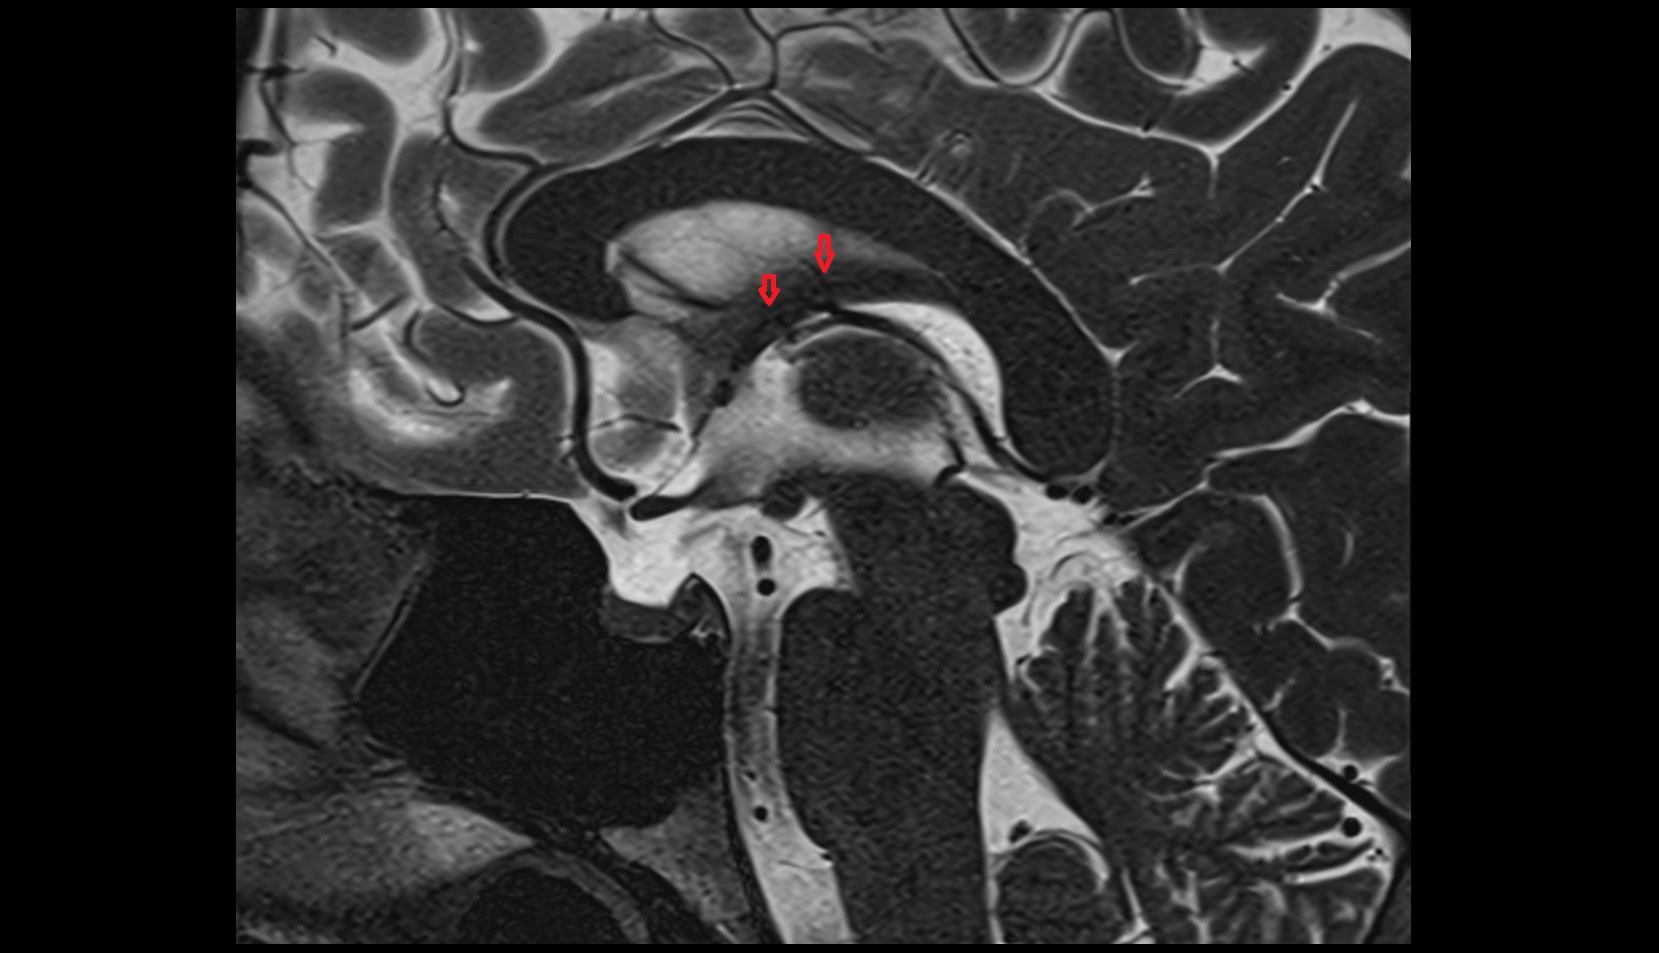

- Body of hippocampus

- Head of hippocampus

- Tail of hippocampus

- Hippocampus